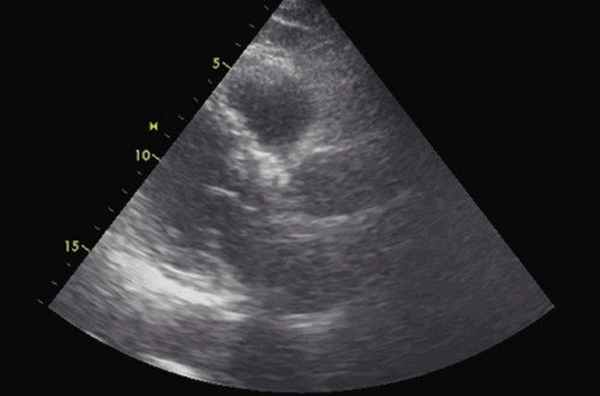

Трансторакальная ЭхоКГ проводилось по традиционной методике на ультразвуковом сканере экспертного класса с использованием мультичастотного микроконвексного датчика с частотой 2-4 МГц в продольном парастернальном сечении. В качестве верифицирующей методики применялась мультиспиральная компьютерная томография (МСКТ).

Помимо гипертрофии миокарда левого желудочка, склеротически измененных створок аортального клапана и наличия его недостаточности I степени, обращало на себя внимание расширение восходящего отдела аорты до 4,5-5,1 см (на различных уровнях) (рис. 1). Исследование средних отделов восходящей аорты (рис. 2) позволяло выявить нитевидную, невыраженно флотирующую структуру, расположенную по передней стенке аорты, формирующую истинный и ложный каналы аорты, которые более детально верифицировались в режиме ЦДК (рис. 3). В слепом участке ложного канала определялись тромботические массы. При исследовании из супрастернального доступа в области дистального отдела восходящей аорты и ее дуги лоцировался участок отслоения интимы (рис. 4). В остальных отделах аорты, доступных для визуализации, патологии выявлено не было. Таким образом, ультразвуковое исследование сердца позволило диагностировать расслаивающую аневризму восходящего отдела и дуги аорты (тип II по De Bakey). Проведенная МСКТ подтвердила данный диагноз (рис. 5).

Рис. 2. Эхокардиограмма больного Ж. Парастернальная позиция по длинной оси с фокусом на восходящий отдел аорты.

1 - отслоенная интима аорты, 2 - истинный канал аорты, 3 - ложный канал аорты, 4 - тромботические массы в слепом участке ложного канала аорты.